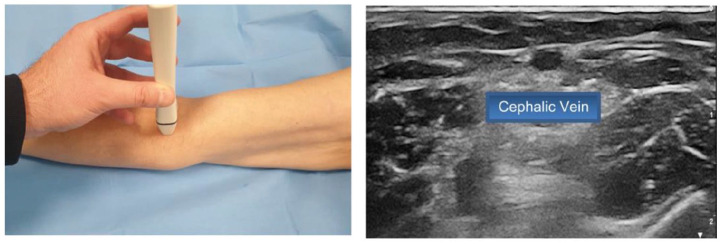

外周置入中心导管(PICC)的插入可能会带来直接/早期不良事件的风险,其中有些风险很小(重复穿刺),有些则很严重(意外动脉穿刺或神经相关损伤)。在插入过程中采取的几种策略可将此类事件的风险降至最低,包括感染、静脉血栓或导管脱落和/或错位等后期并发症风险。本文介绍了 SIP 协议(PICC 安全插入)的更新版本,该插入捆绑包包括八种有效策略,旨在最大限度地减少与插入相关的即时、早期或晚期并发症。这些策略包括:利用 RaPeVA(快速外周静脉评估)方案进行术前超声评估;适当的皮肤消毒技术;选择适当的静脉,采用 Zone Insertion Method™(区域插入法);明确识别正中神经和肱动脉;超声引导下穿刺;超声引导下的尖端导航;术中评估尖端位置;正确固定导管以及适当保护出口部位。这一更新版 SIP 方案包括几项基于 PICC 插入最新循证科学文献的新技术,如隧道技术的临床实用性、术中尖端导航和尖端位置超声的使用,以及出口部位保护(氰基丙烯酸酯胶)和导管固定(皮下固定)的新技术。

Insertion of Peripherally Inserted Central Catheters (PICCs) is potentially associated with the risk of immediate/early adverse events, some of them minimal (repeated punctures) and some relevant (accidental arterial puncture or nerve-related injury). Several strategies adopted during the insertion process may minimize the risk of such events, including late complication risks such as infection, venous thrombosis, or catheter dislodgment and/or malposition. This paper describes an update version of the SIP protocol (Safe Insertion of PICCs), an insertion bundle which includes eight effective strategies that aims to minimize immediate, early, or late insertion-associated complications. These strategies include: preprocedural ultrasound assessment utilizing the RaPeVA (Rapid Peripheral Venous Assessment) protocol; appropriate skin antiseptic technique; choice of appropriate vein, adoption of the Zone Insertion Method™; clear identification of the median nerve and brachial artery; ultrasound-guided puncture; ultrasound-guided tip navigation; intra-procedural assessment of tip location; correct securement of the catheter, and appropriate protection of the exit site. This updated version of the SIP protocol includes several novelties based on the most recent evidence-based scientific literature on PICC insertion, such as the clinical relevance of the tunneling technique, the use of ultrasound for intra-procedural tip navigation and tip location, and the new technologies for the protection of the exit site (cyanoacrylate glue) and for the securement of the catheter (subcutaneous anchorage).